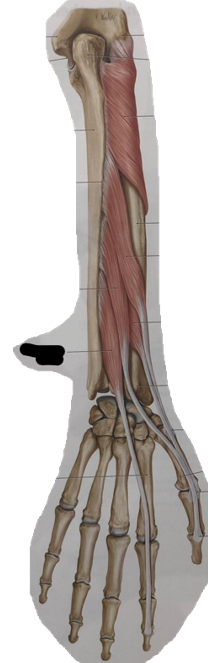

anatomie elleboog (spieren) (learn mode)

m. supinator (supinatie)

m. abductor pollicis longus (supinatie)

m. extensor pollicis brevis (supinatie)

m. extensor pollicis longus (supinatie)

m. extensor indicis (supinatie)

m. pronator quadratus (pronatie)

m. flexor carpi radialis (pronatie)